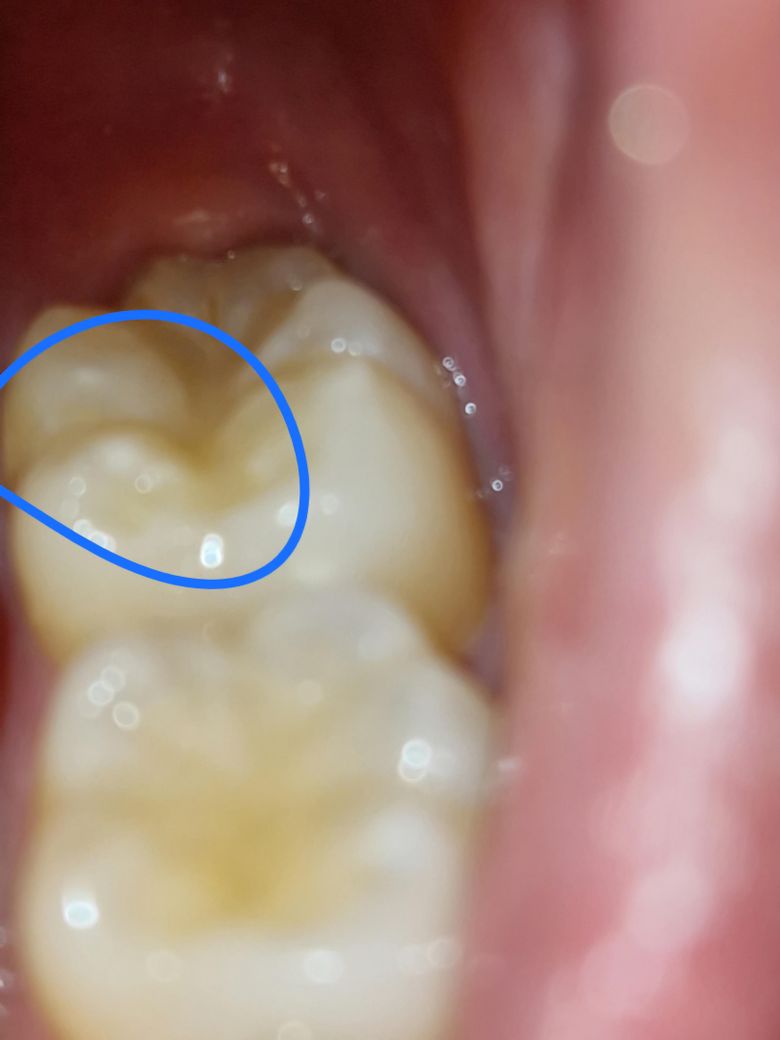

자고 일어나니 알맹이 씹는 느낌과 함께 바스락 소리가 나더니 치아가 저렇게 하얀 부분이 생기고 뭉특해진 것 같아요. 레진으로 떼운 곳인데 단순히 레진이 벗겨진 건가요? 불편함은 딱히 없는데 다시 레진으로 씌우는 조치를 취할 수 있나요?

• 1번 째 사진

사진이 흐려 확실히 안보입니다. 만약 레진이 떨어졌다면 떨어진 그부위만 도로 떼우면 됩니다.

사진상으로는 크게 문제가 잇어 보이는건 없는거 같습니다. 기존에 치료햇던거 떨어졋을수도 잇으니 치과에 가셔서 검진만 한번 받아보세요.

레진으로 떼운 부위인지 아니면 치아 교두일지는 사진상으론 정확하지 않으나 어쨌든 충치가 있거나 크게 깨진것은 아닌듯 하여 다듬어주거나 레진으로 다시 떼워주면 될 것 같습니다

딱딱하거나 질긴 음식은 주의하셔야 합니다

사진상으로는 특별히 문제점은 모르겠으나 레진이 깨진 경우에는 다시 수복을 하시면 됩니다.

치아 표면에 충전된 재료가 떨어지게 되면 까끌거리는 느낌이 들 수 있거나 파의 느낌이 들 수 있습니다. 또한 치아가 파절 됐을 경우에도 해당 증상이 나타날 수 있습니다. 자세한 확인을 위해서 치과에서 진료를 받아보는 것을 권유 드립니다.